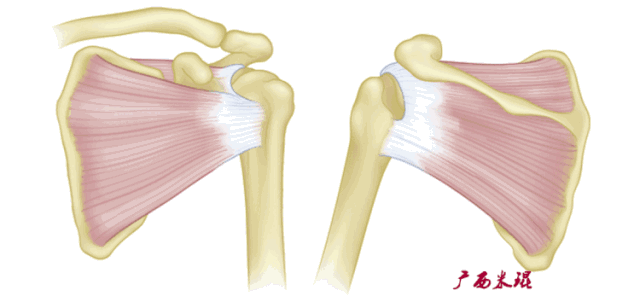

肩袖(Rotator cuff)损伤由Smith于1834年发现并命名,指组成肩袖的冈上肌、冈下肌、肩胛下肌和小圆肌的损伤。肩袖是以上4条肌腱共同组成的功能复合体,呈一个袖套状包绕肱骨头,维持盂肱关节的稳定,同时提供肩关节活动时所需的动力。

冈上肌主要功能是肩关节外展,当然外展功能还需要三角肌等协助。

冈下肌和小圆肌的主要功能是肩关节外旋,肩胛下肌的主要功能则是肩关节内旋,旋转袖由此而来。冈上肌、冈下肌、肩胛下肌或小圆肌的断裂会导致其相应功能的受损。